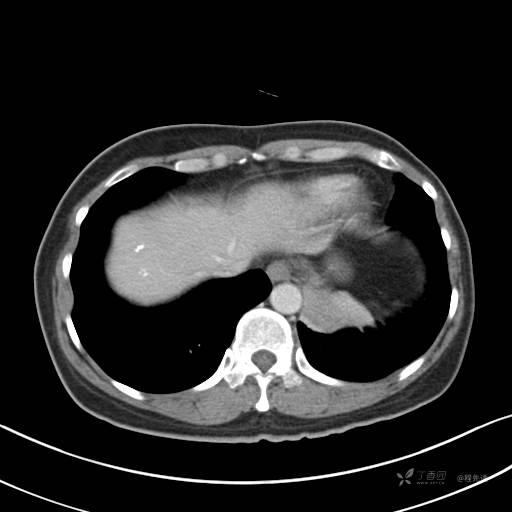

CT平扫

纵隔窗

病灶平扫CT值约31HU